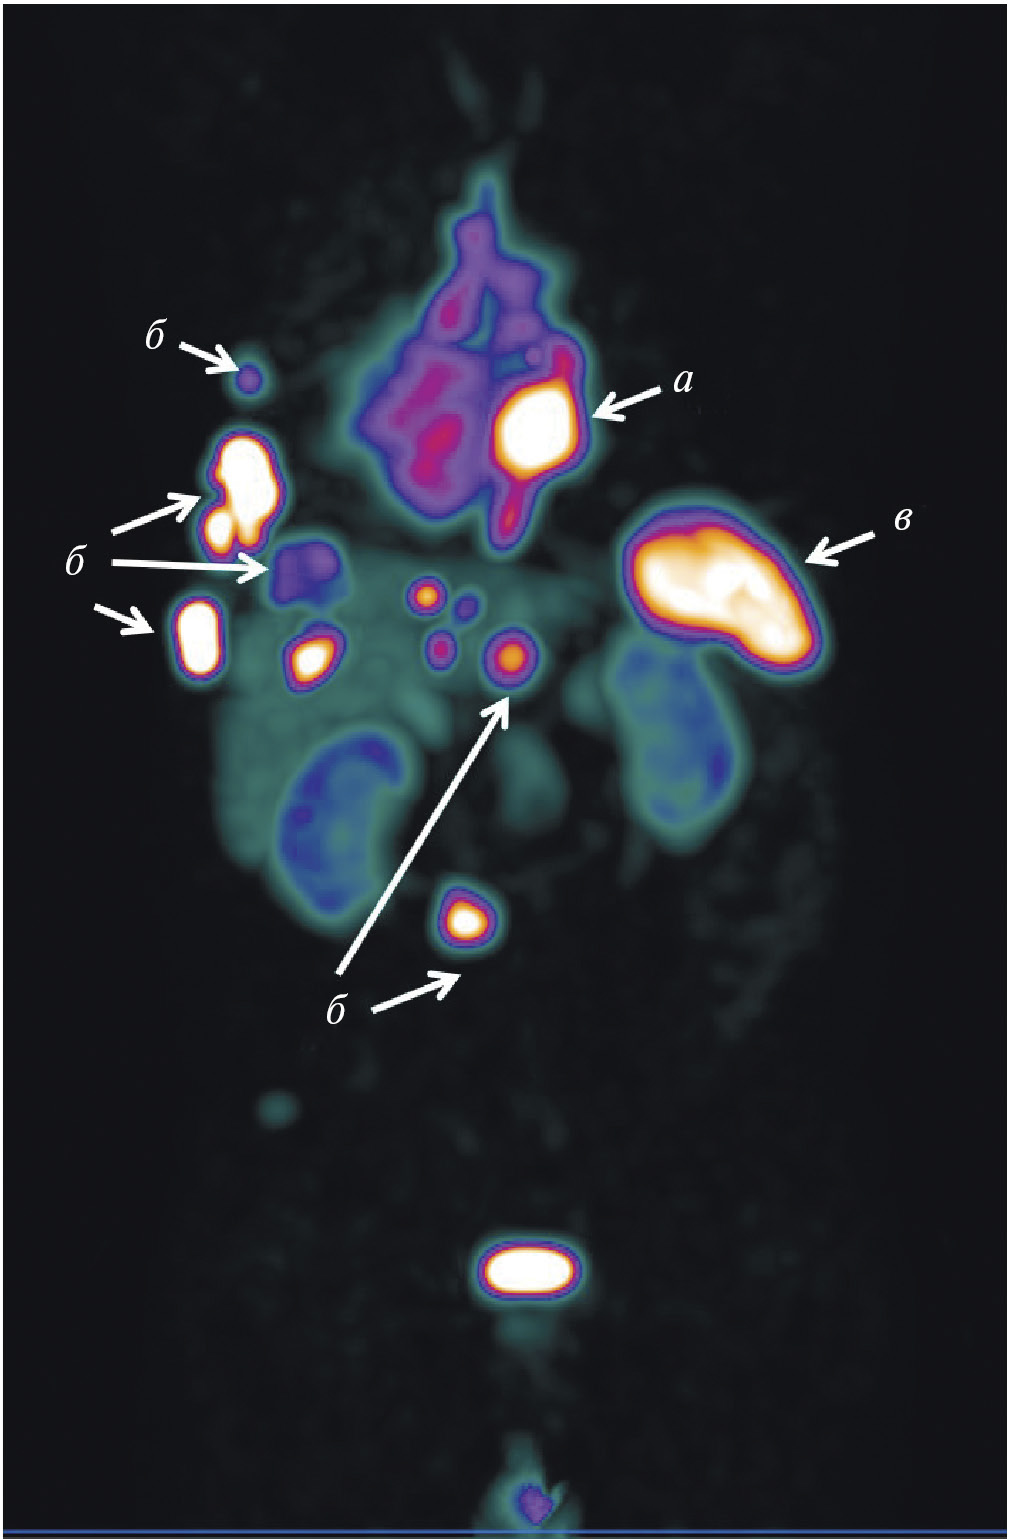

В мировой ядерной медицине для сцинтиграфии обычно применяют 111In-пентетреотид, или 111In-октреотид ([111In-DTPA]octreotide, OctreoScan, Tyco Healthcare, США; АО “Фармсинтез”, Россия). Основные показания к его использованию — стадирование, рестадирование и мониторинг лечения нейроэндокринных SSTR-позитивных опухолей. В последние годы 111In-пентетреотид служит для радионавигации при хирургическом лечении новообразований с гиперэкспрессией соматостатиновых рецепторов. К сожалению, физические характеристики индия-111 (длительный период полураспада, неоптимальный для регистрации на гамма-камере спектр излучения, высокая стоимость циклотронного производства) ограничивают его применение в радионуклидной диагностике. В связи с этим не подвергается сомнению актуальность создания в России меченного технецием-99м октреотида для ОФЭКТ-диагностики нейроэндокринных опухолей. Разработкой такого радиофармпрепарата в рамках проекта федеральной целевой программы “Фарма-2020” занимался ТПУ в сотрудничестве с НИИ онкологии Томского НИМЦ. Клинические испытания отечественного 99mТс-октреотида продемонстрировали его высокую эффективность при диагностике и стадировании НЭО (рис. 3). В настоящее время набор для приготовления этого РФЛП зарегистрирован в России под названием “Нейроскан, 99mТс”, а его производство налажено в ТПУ.

Рис. 3. ОФЭКТ/КТ с 99mТс-октреотидом пациента с нейроэндокринным раком лёгкого: а — конгломерат первичной опухоли и метастазов в лимфатические узлы; б — метастазы в кости; в – селезёнка

Для ПЭТ-диагностики нейроэндокринных опухолей нашли применение аналоги соматостатина, меченные 68Ga. При этом наиболее популярными стали 68Ga-DOTATATE и 68Ga-DOTATOC. Сравнительная оценка диагностической эффективности выявила их практически одинаковую точность, однако уровень аккумуляции 68Ga-DOTATOC в опухоли оказался выше [16]. При гиперэкспрессии SSTR2 и SSTR5 предпочтение следует отдавать 68Ga-DOTANOC, который характеризуется более высокой афинностью к этим рецепторам [17]. Для ПЭТ-диагностики нейроэндокринных опухолей также перспективны 64Cu-DOTATATE [18] и 18F-FP-Gluc-TOCA [19].